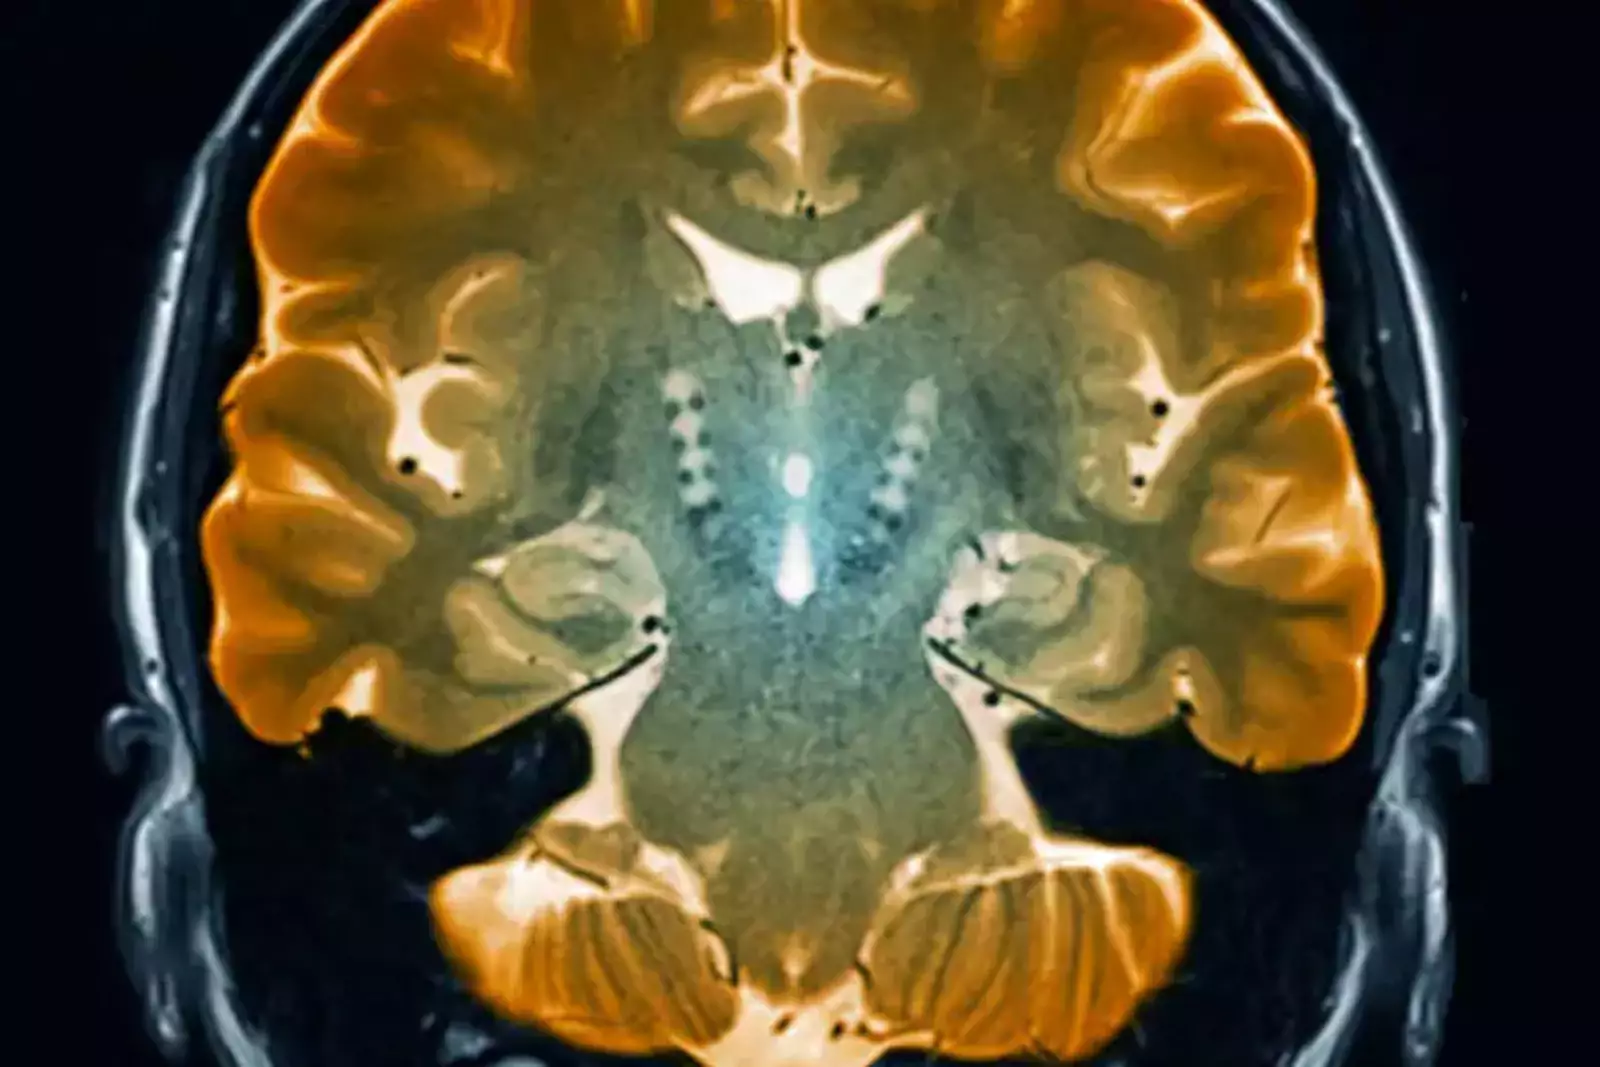

Ученые из института Броуда и Гарварда (США) обнаружили новый тип клеток мозга, погибающих при болезни Паркинсона. Находка стала возможной благодаря новой методике, позволяющей определить, какие гены активны в отдельных клетках.

Болезнь Паркинсона — это прогрессирующее состояние, которое связано с постепенной гибелью клеток в части мозга, называемой черной субстанцией.

Соответствующие клетки вырабатывают сигнальное химическое вещество под названием дофамин, участвующее в контроле движения, однако до сих пор не было известно, какие эти конкретно клетки.